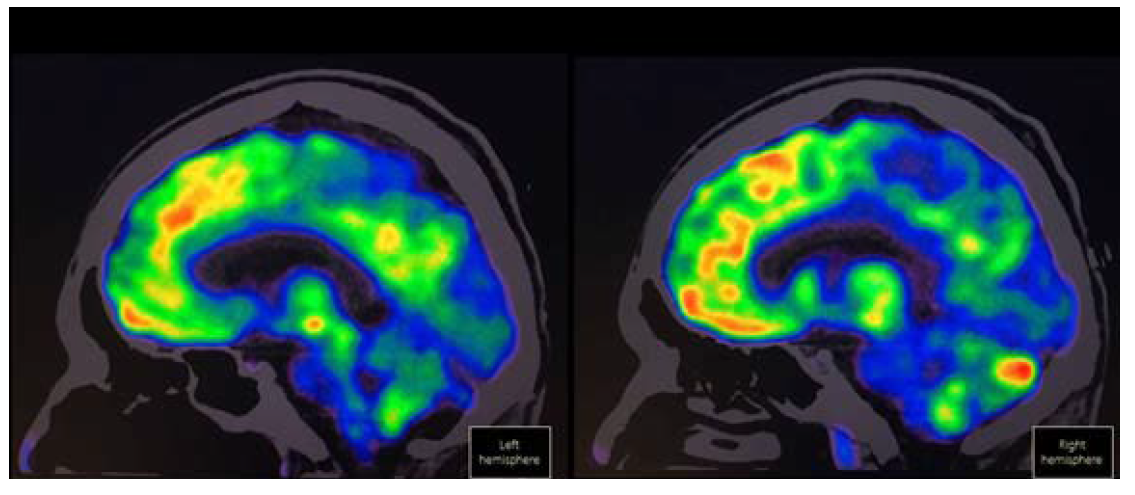

La tomografía por emisión de positrones con 18-fluorodesoxiglucosa (18-FDG PET) debe ser considerada para el diagnóstico de encefalitis límbica cuando la IRM resulta ser normal.3 En la encefalitis anti-NMDAr puede mostrar metabolismo cerebral con gradiente frontooccipital disminuido en regiones mediales de los lóbulos occipitales.59 La utilización de esta herramienta ha sido defendida por algunos autores puesto que puede ser útil para el diagnóstico y en la búsqueda de tumores asociados. Si bien la detección del anticuerpo anti-NMDAr en el LCR es el biomarcador de elección, el hipometabolismo occipital medial puede ayudar en el abordaje y seguimiento de los pacientes59 (Figura 4). La Figura 5 resume cómo realizar el procedimiento diagnóstico de los pacientes con sospecha de encefalitis anti-NMDAr.

Figura 4 18-FDG PET en un hombre de 37 años con encefalitis anti-NMDAr definitiva, manifestada por cuadro clínico de predominio psicótico con síntomas nihilistas y catatónicos, quien muestra hipometabolismo occipital medial.